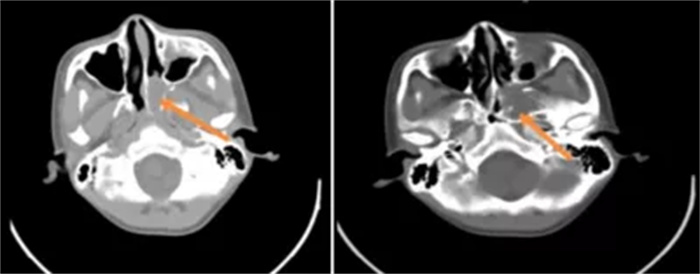

入院后,医生为患者进行了鼻腔填塞,但仍间断有活动性出血,查血结果显示他已轻度贫血。后经鼻内窥镜检查,主管医生杜经纬考虑其患有鼻咽纤维血管瘤。

由于肿瘤范围广、手术风险大,该院耳鼻咽喉头颈外科科主任彭涛组织神经外科、影像科、肿瘤科、口腔颌面外科、介入医学科、输血科等科室开展多学科会诊讨论患者病情。经过详细讨论,诊断该名患者患有鼻咽纤维血管瘤,拟在鼻内窥镜下手术切除肿瘤。